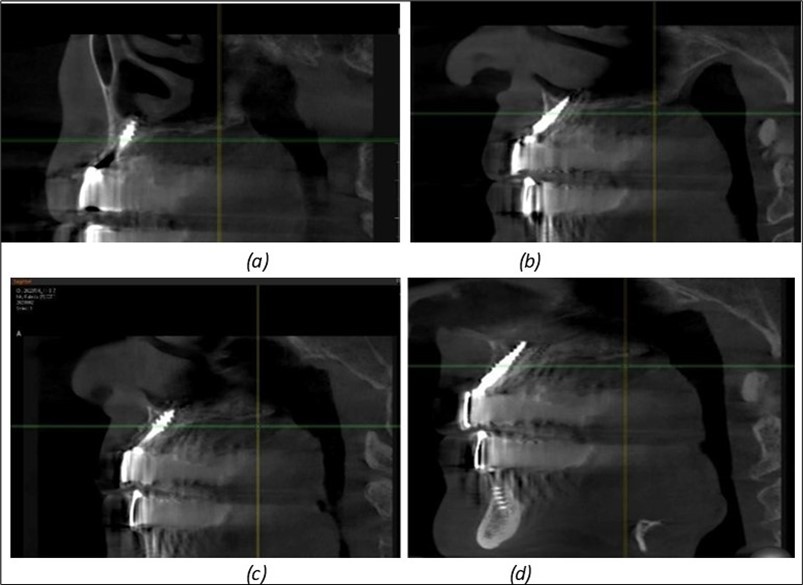

Figure 13.Corticobasal BCS implants fixed between the vestibular and lingual cortices with support on the basal bone: (a) BCS fixed between the lateral cortices; (b) BCS implant with support on the basal cortex.

Figure 14.Rx panoramic final situation control: (a) Panoramic X-ray with the addition of a distal BCS implant in quadrant 3 at 11.2022; (b) Control X-ray, 10.2023.